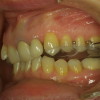

Viele Patienten befinden sich wegen chronischer Schmerzen im Kopf-, Gesicht-, Hals-, Rückenbereich in Behandlung. Bei einem großen Teil dieser Patienten wurde häufig nur eine symptomatische Behandlung eingeleitet und der Ursache nicht auf den Grund gegangen. Eine der Ursachen dieser Schmerzen kann eine Fehlfunktion im Kauorgan mit Beteiligung des Kiefergelenks sein, die so genannte Cranio-Mandibuläre Dysfunktion (CMD).